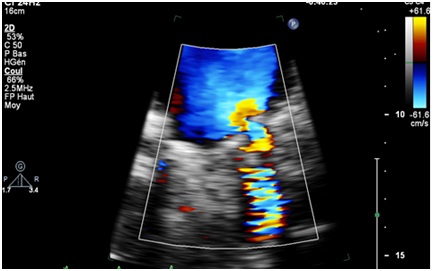

The Contribution of Echocardiography in the Dysfunctions of Mechanical Prosthesis: Report of 11 Cases

Saloua Oummou*, Abir Abardazzou, Salwa Karimi, Dounia Benzeroual, Mustapha Elhattaoui